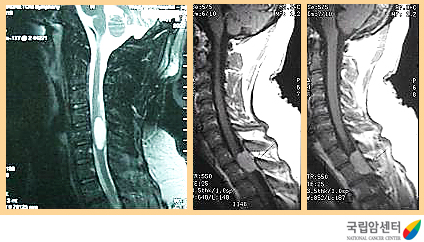

현재까지 진단 방법 중 가장 정확한 방법입니다. 자기공명영상촬영(MRI)은 전산화단층촬영(CT)에 비해 근육, 인대 등의 연부조직의 대조가 뛰어나고 횡단영상 뿐만아니라 관상영상과 시상영상 등 원하는 어떠한 단면의 영상도 얻을 수 있기 때문에 척수종양의 크기나 범위 낭포성 변성을 쉽게 판단할 수 있습니다. 조영증강에 의해 대부분의 병소가 더욱 명확해지며, 다발성 경화증, 척수경색증, 정맥울혈, 출혈, 척수염 등은 자기공명영상(MRI)상 척수의 팽대와 척수내 조영증강되는 음영을 볼 수 있어 종양과의 구별이 어려운 때가 있습니다.

[경추부와 흉추부에 발생한 경막외 수막종의 자기공명 영상 촬영 소견]